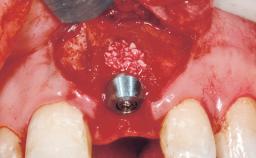

Immediate Flapless Placement of an Implant in a Maxillary Left Central Incisor Site

A 42-year-old female patient was referred to our clinic at the School of Dentistry of the University of São Paulo in November 2004, presenting a deficient restoration in the upper left central incisor. The clinical examination revealed no gingival retraction or any signs of gingival inflammation and, therefore, previous periodontal treatment was not considered. The patient presented a high lip line at full smile and a thin tissue biotype. This combination characterized a high-risk situation from an anatomic point of view, which required careful preoperative planning and cautious surgical execution.

Placement Protocol Immediate implant placement

Bone Volume Sufficient, with intact walls